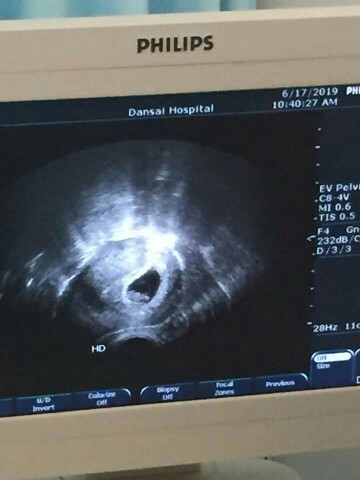

อัลตราซาวด์ 7 weeks เห็นแค่ถุงตั้งครรภ์ ผิดปกติมั้ยคะ ?

ซาวด์ทางหน้าท้องหรือช่องคลอดคะแม่ ถ้าทางหน้าท้อง ถ้าตัวอ่อนยังเล็กมากๆ หรือเป็นคนหน้าท้องหนา อาจจะยังไม่เห็นค่ะแม่ ทางช่องคลอดจะพอมีลุ้นมากกว่าค่ะ ทั้งนี้เป็นไปได้ว่า อายุครรภ์อาจจะน้อยกว่าที่นับ เพราะไข่อาจจะตกช้ากว่ากำหนด ตัวอ่อนยังเล็กมากอยู่ จึงยังไม่พบ ก็เป็นได้ค่ะแม่ ทานโฟลิคทุกวัน พักผ่อนเยอะๆ นะคะ ซาวด์ครั้งหน้าอาจจะได้เจอกันแล้วจ้า

Đọc thêmสำหรับเราไม่ผิดปกติ (แต่บางคน6-7wนี่ก็จะเห็นตัวอ่อนด้วยแล้ว) บ้านนี้ตอน4wเห็นแค่ถุง พอ9wก็เห็นตัวกับหัวใจแล้วค่ะ

น้องอาจจะตัวเล็กเลยยังไม่เห็นค่ะ สัก9wไปซาวด์ดูใหม่นะคะ

บ้านนี้ตอน7วีค ก็ไม่เจอค่ะ มาเจอตอน13วีคพอดีน้องแอบเก่ง😂

น้องอาจจะยังตัวเล็กอยู่ค่ะ

ซาวผ่านช่องคลอดตอน 7w เห็นหัวใจดวงน้อยๆเต้นเเล้ว ตอนนี้ได้21wเเล้วค่ะ